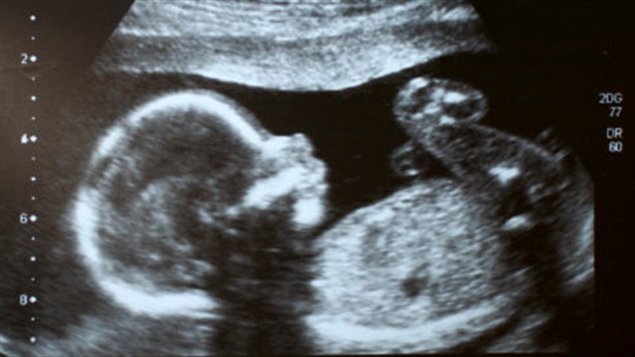

Il y a à peine quelques années, l'échographie était le seul procédé offert aux femmes enceintes afin de connaitre le sexe de l'enfant qu'elles portaient Ainsi, la majorité des futures mères attendaient jusqu'à la moitié de leur grossesse pour réaliser une échographie qui confirmerait le sexe du bébéIl est possible d'avoir une indication sur le sexe de votre enfant lors de votre échographie du premier trimestre en observant l'aspect du tubercule génital du fœtus Cette méthode, dite du bourgeon génital donne de bons résultats, en particulier pour les échographies réalisées à partir de 11 semaines de grossesse (13 semaines dCette façon de faire estelle fiable ?

Et comme tout parent, l'envie de savoir s'il s'agit d'une fille ou d'un garçon Mais estce que le gynécologue estil déjà dans la capacité de dire le sexe de bébé ?C'est possible On peut déjà se faire une petite idée du sexe à l' échographie des 12 semaines Au cours de cet examen, le médecin scrute les différents organes, notamment le tubercule génital Un certain nombre de travaux ont démontré que son inclinaison pouvait laisser supposer le sexe duComment déterminer le sexe de son bébé Devenir parent est un moment passionnant dans la vie de toute personne Vous avez certainement envie de connaitre son sexe avant sa naissance afin que vous puissiez mieux vous préparer et pour lui

Avant la 14e semaine de grossesse, il existe d'autres méthodes que l'échographie pour identifier le sexe du fœtus A l'aide du dépistage prénatal (p ex la choriocentèse), les gynécologues peuvent savoir dès la 10e ou 11e semaine si la future maman est enceinte d'une fille ou d'un garçonIl est effectivement possible de voir le bourgeon sexuel (et non le sexe réellement) à l'échographie des 12 semaines, et en fonction de sa position de donner une présomption de sexe Mais des erreurs sont possibles Néanmoins ce n'est qu'à l'échographie des 22 semaines qu'on voit vraiment le sexe et que l'on peut être certainEt voilà toutes nos félicitations vous êtes enceinte Maintenant vous aimeriez bien savoir si bébé est une fille ou un garçon, pour commencer a choisir le prénom, la décoration, et aussi faire passer le temps en attendant son arrivée Le plus simple et le plus certain reste l'échographie de morphologie pour connaitre le sexe de bébé

Plusieurs études scientifique ont évalué son taux de réussite (voir en anglais uniquement, une étude qui date de 1999, une de 06 et une de 12) La conclusion principale est que la méthode du bourgeon génital donne de bons résultats pour les échographies réalisées à partir de 11 semaines d'aménorrhées (9 semaines de grossesse) et pourLe moment auquel est pratiqué l'échographie a son importance En fonction du stade de la grossesse, le spécialiste ne sera pas à la recherche des mêmes élémentsLe clan du oui Comme la majorité des gens, vous avez tellement hâte à la e semaine de grossesse pour enfin connaître le sexe de ce petit être qui grandit dans votre ventre!